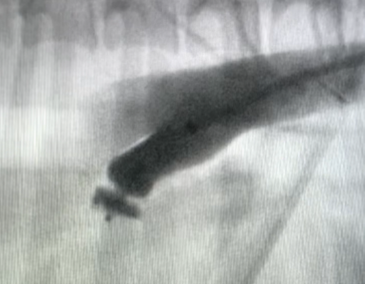

Step three: A delivery sheath is positioned across the PDA into the pulmonary artery, and the ACDO device is inserted through the sheath. The distal disc of the ACDO is exposed before the sheath and ACDO device are then retracted together until the distal disc meets the pulmonary opening of the PDA (Figure 5). The ACDO device is held in place while the delivery sheath is retracted, deploying the waist of the device into the MDD of the PDA and the proximal disc within the ductal ampulla (Figure 6). Gentle to-and-fro manipulation of the device delivery cable is applied to ensure correct positioning.